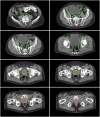

FIGURE 4.

Examples of 68Ga-PSMA-11–positive disease outside radiation fields on CT (top), PET (middle), and PET/CT (bottom). Once positive lesions were identified on PET, contours of prostate CTV (yellow) and pelvic LN CTV (green) were drawn on the basis of CT. (A) Primary prostate tumor (MTV, 3 cm3; SUVmax, 12) without CT correlate, located more than 1 cm below CTV. (B) Right perirectal LN (short axis, 8 mm; SUVmax, 6.1). (C) Multiple abdominal LNs (short axis, 4–7 mm; SUVmax, 4.7–17.2). (D) Multiple left subclavicular LNs (short axis, 3–4 mm; SUVmax, 3.0–9.1). (E) Sacral bone metastasis without CT correlate (SUVmax, 8.4). (F) Left lung nodule (short axis, 7 mm; SUVmax, 1.5).